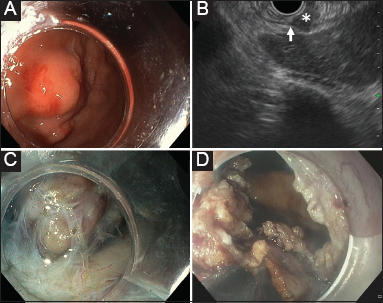

A 75-year-old woman was admitted for evaluation of an asymptomatic submucosal lesion of the gastric body. Endoscopic ultrasonography (EUS) showed a 1 cm in size hypoechoic lesion originating from the muscularis propria. Fine-needle biopsy (FNB) with a novel 22-G histology needle (Olympus EZ shot 3 plus, Tokyo, Japan) disclosed a glomus tumor (Fig. 1 and 2). Given the potential risk of malignancy, the lesion was further removed by laparoscopic endoscopic cooperative surgery (LECS), as previously described [1]. The lesion was partially enucleated with a Flush Knife BTs 1.5 mm (Fujifilm, Tokyo, Japan). A clip with dental floss was applied to the center of the lesion for countertraction, and then a full thickness excision was performed with an IT knife nano (Olympus). The lesion was then retrieved with a snare and the site of resection was sealed internally with endoscopic clips, and externally with absorbable laparoscopic sutures. The patient was discharged on postoperative day 2 and had an uneventful recovery. Histology confirmed the initial diagnosis.

Figure 2 Endoscopic images. (A) Submucosal tumor of the anterior wall of the gastric body. (B) Endoscopic ultrasound showed that the tumor (asterisk) originated from the muscle layer (arrow). (C) Partial enucleation of the tumor confirmed the strong attachment to the muscle layer. (D) Full thickness incision with IT knife of the last bridge of tissue